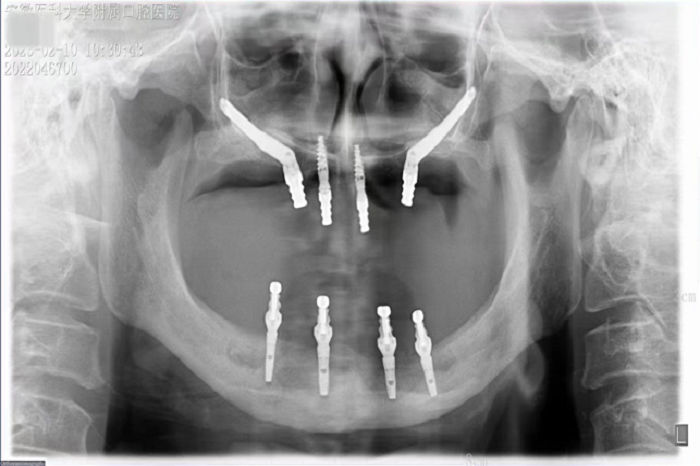

2月8日,色色啦 种植科主任刘鑫带领其团队完成一例上颌骨“穿颧”、下颌神经游离种植手术。该手术是继2019年种植科完成首例穿颧种植术后的第二例穿颧种植。

据悉,患者潘女士54岁,由于重度牙周炎导致全口牙齿缺失,严重影响面容及咀嚼功能,因颌骨严重萎缩无法进行活动义齿修复,遂来色色啦 种植科要求行上颌稳固的修复。通过检查发现潘女士上下颌骨骨量严重不足,经反复比对和考量,刘鑫主任制定了对患者上颌骨进行穿颧种植修复、下颌骨通过神经游离进行种植的方案。经过患者与家属深思熟虑后,接受了行穿颧种植术的建议。治疗组通过专业三维设计软件规划植体,口腔颌面外科和种植科专家共同完成了穿颧种植手术。患者术后第一天情况良好,无明显肿胀,精神状态佳。